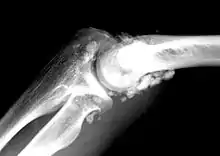

X-ray of an elbow affected by synovial chondromatosis

In the early stages of the disease it is often confused with tendinosis and/or arthritis. Once it reaches transitional the loose bodies become apparent with X-ray in greater than 70% of cases, with MRI often showing where xray fails. In experienced hands, ultrasound is also useful for the diagnosis.[2]